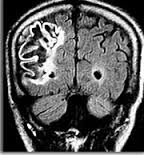

Les lésions en cause peuvent être vasculaires, tumorales, traumatiques ou infectieuses (abcès cérébral). Les hémiplégies d’origine vasculaire sont les plus fréquentes ; c’est ce que l’on appelle un AVC (Accident vasculaire cérébral). La lésion peut être ischémique, par obstruction vasculaire (embolie ou thrombose), ou hémorragique (rupture d’anévrisme cérébral).

Les hémiplégies d’origine vasculaire ont un début brutal, et peuvent régresser plus ou moins complètement ; les hémiplégies tumorales s’installent lentement et s’aggravent progressivement.